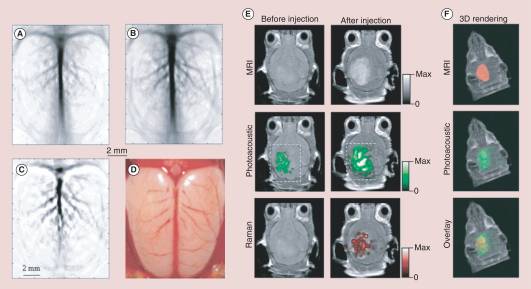

In the sequel, to describe our approach, we will mainly focus on the acoustic imaging using micro-bubbles, i.e. (1), and the photo-acoustic imaging using (dielectric) nano-particles, i.e. (3). In Figure 1 and Figure 2, we see the sharpness of the images when injecting nano-particles or micro-bubbles respectively in the targeted regions. This suggests, in particular, that contrasting the images taken before and after injecting the small-scaled contrasts agents would allow us to extract quantitative information on the targeted regions, as the mass density and the bulk modulus, for the acoustic imaging, or the electric permittivity, and eventually the conductivity, for the photo-acoustic imaging of the targeted region. Our aim is to understand and quantify this.

Refer to caption

Figure 1. Non-invasive photo-acoustic imaging of a rat’s cerebral cortex using nano-particles as contrast agents. This figure is from [49].